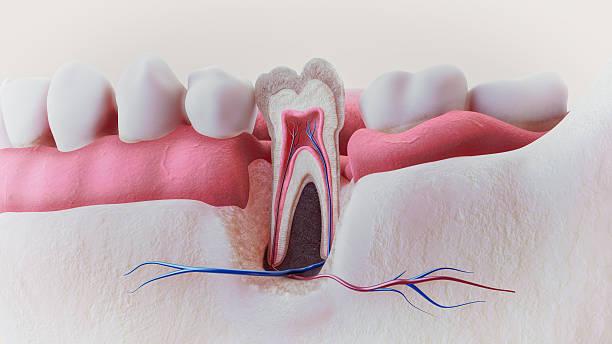

Root canal treatment removes infected pulp from inside the tooth. The pulp contains nerves and blood vessels essential for tooth health. Infection in this area can lead to swelling, severe pain, and eventual tooth loss. By cleaning and sealing the canals, the tooth is restored and protected from future infection.

How Root Canal Treatment Works